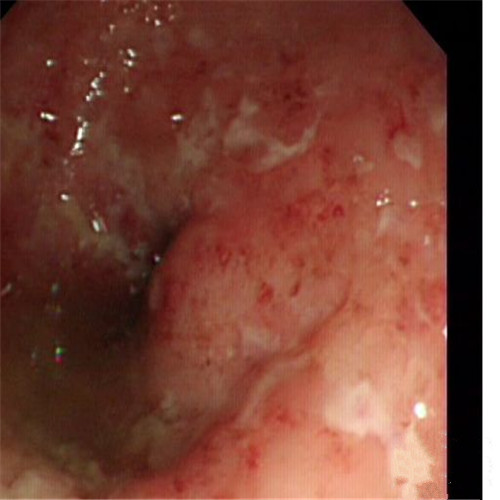

潰瘍性結腸炎重度糜爛